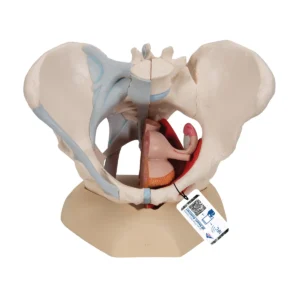

3B Female Pelvis Skeleton Model